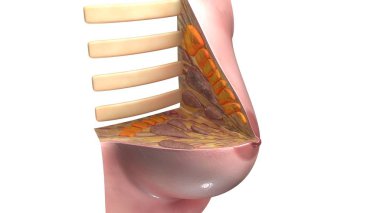

Tıbbi konsept 3 boyutlu illüstrasyon için insan kadın kas anatomisi

KasBileşenlerDorsalfleksörPalmarbrachiiBrevisLongusabdüktöradductorekstansiyonOrasına3d oluşturma3B illüstrasyonCarpiteresdeltoideusDigitorumbrachioradialiskomplikasyondigitiquintipollicisprofundusulnarispronatorPalmarisinterosseiopponenscoracobrachialisKas Anatomisilongus muscleinterossei musclebrevis musclelummbrical muscletricep mucslepollicis musclesuperficialis muscleBenzer İçerikler